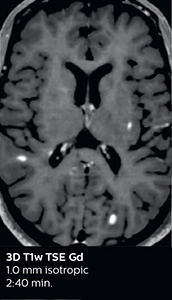

Fast MS protocol with optional sequences

The abbreviated MS protocol for brain is only around 9 minutes, so in case of suspected multiple sclerosis, one or two more advanced sequences may be added, such as PSIR (phase sensitive inversion recovery) or susceptibility-weighted sequences to help us make more confident diagnoses in these inflammatory cases.

In this example, the optional 3D multishot susceptibility weighted sequence with 0.6 mm isotropic voxels is 2 lesions with a central vein sign (arrows) and one lesion with a phase-rim sign (arrowhead). The total scan time, including SmartBrain and axial PD/T2 3mm, is 11:10 min. and is 18:30 min. with the optional 3D PSIR and 3D SWI multishot included.

3D TFE T1

3D FLAIR

DWI

3D T1w TSE Gd

3D PSIR

3D SWI